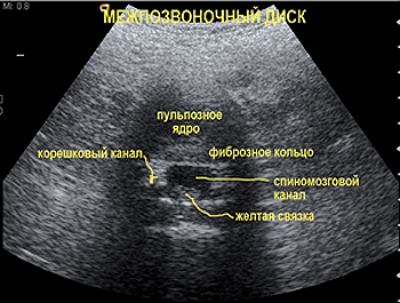

В ходе данной процедуры обследуются не только позвоночник, но и мышцы, сухожилия, а также мягкие ткани в области спины и поясницы.

Что позволяет определить процедура

Что можно увидеть на УЗИ спины?

На УЗИ спины можно увидеть состояние мягких тканей, таких как мышцы и связки, а также оценить наличие воспалительных процессов, опухолей, грыж межпозвоночных дисков и других патологий. УЗИ позволяет визуализировать анатомические структуры и выявить изменения, которые могут вызывать болевой синдром или другие симптомы.